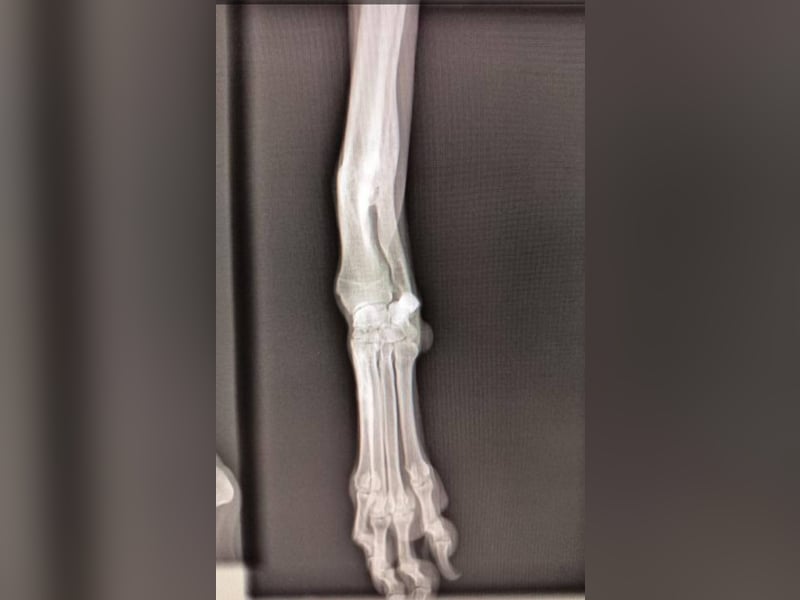

Wahrscheinlich wurde sie aufgrund eines verheilten Bruchs im Vorderbein ausgesetzt. Diese leichte Verletzung hindert sie nicht daran, ein normales Leben zu führen und eine Operation ist nicht notwendig.